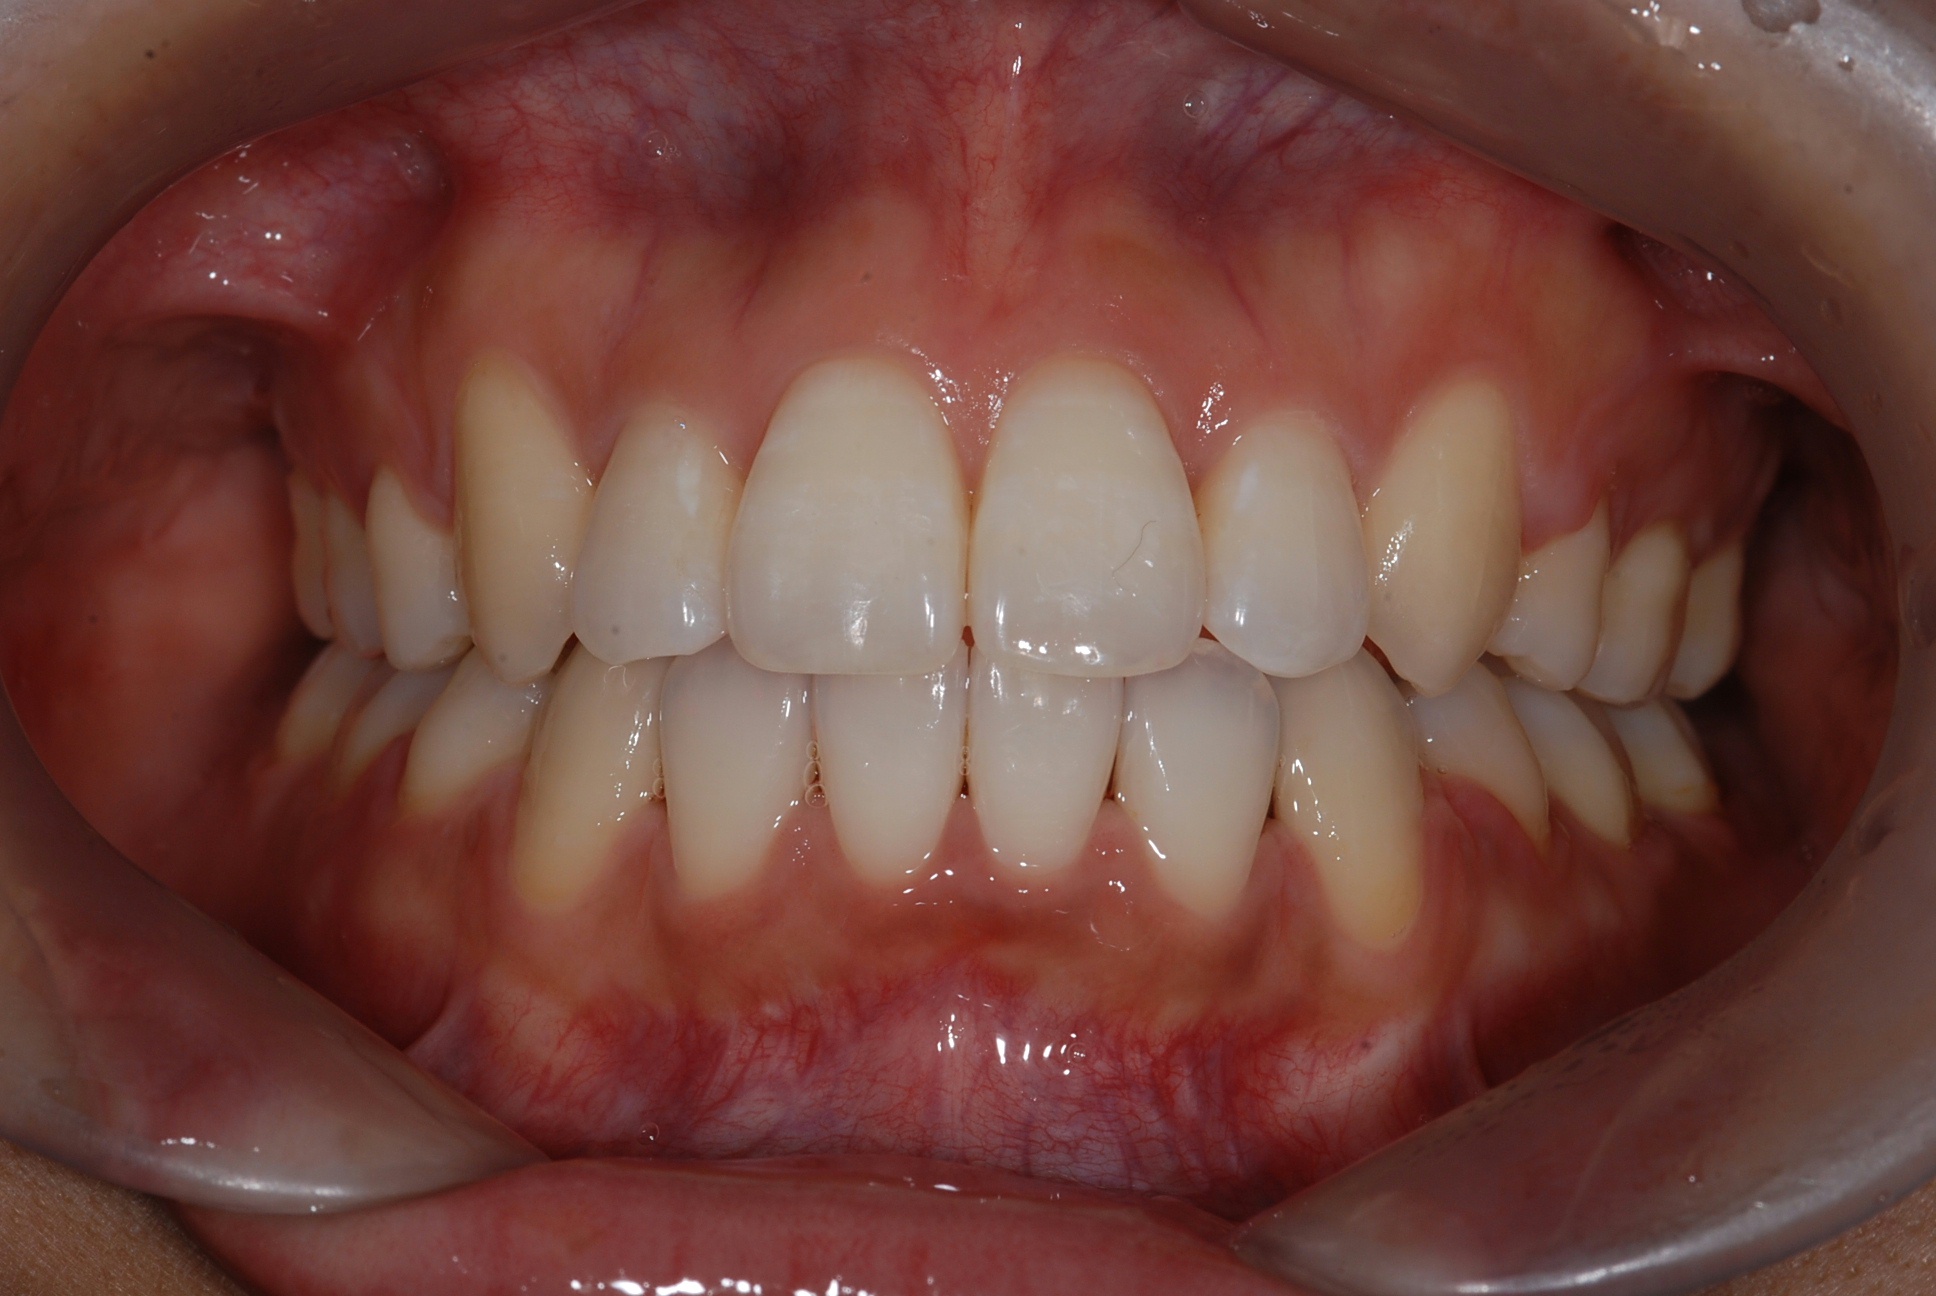

치료 후 사진입니다.